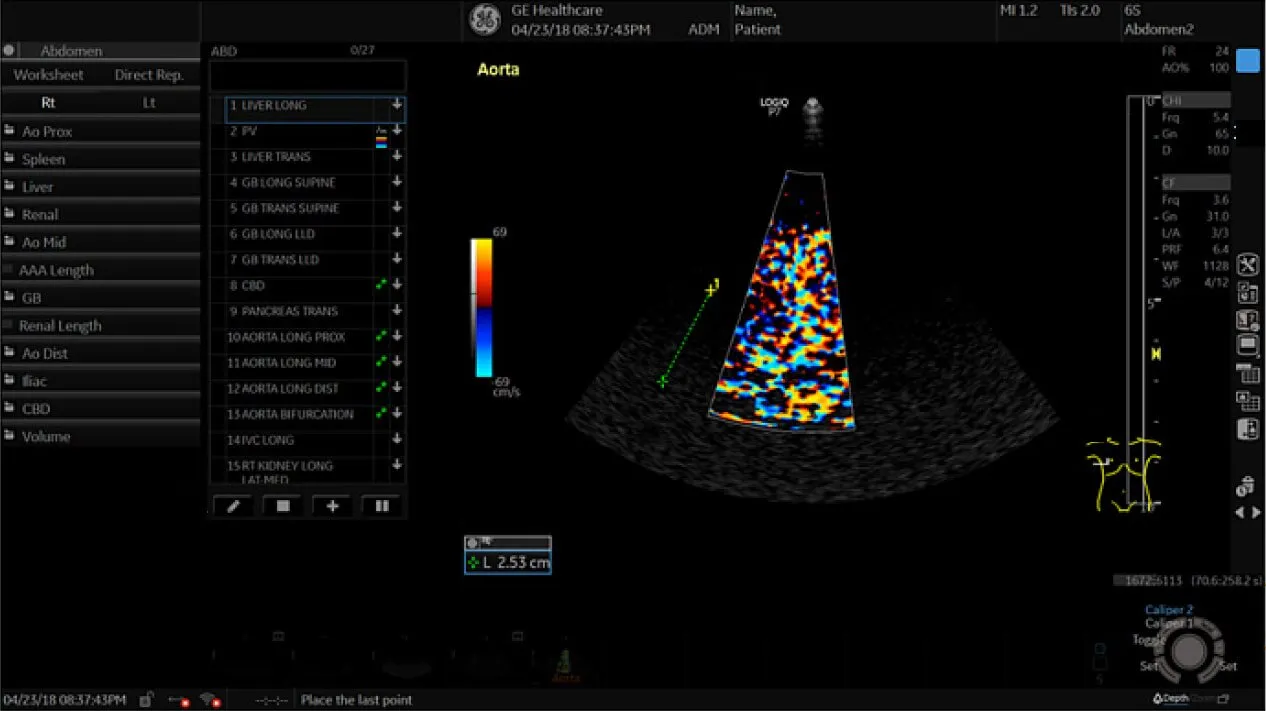

Клинические изображения

Благодаря технологии XDClear клинические изображения становятся более чёткими, с минимальным уровнем шумов и артефактов. Интеллектуальные алгоритмы обработки данных, поддержка мультичастотных датчиков и автоматические функции — такие как допплерография, 3D/4D-визуализация и автоматические измерения — позволяют проводить широкий спектр исследований с высокой точностью. Удобная панель управления, регулируемый монитор и компактные размеры делают использование аппарата максимально комфортным.

- Абдоминальные исследования

- Инновационные инструменты, в том числе недопплеровская визуализация кровотока в B-режиме (B-Flow), 3D/4D сканирование, эластография, стресс-эхокардиография, тканевая допплерография (TVI/TVD) и УЗИ с контрастным усилением (CEUS).